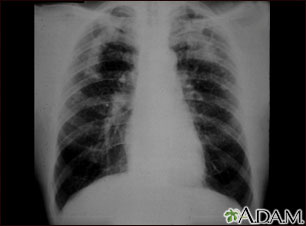

A chest x-ray is an x-ray of the chest, lungs, heart, large arteries, ribs, and diaphragm.

A serial chest x-ray is one that is repeated. It may be done to monitor changes found on a past chest x-ray.

What Abnormal Results Mean

Abnormal results may be due to many things, including: